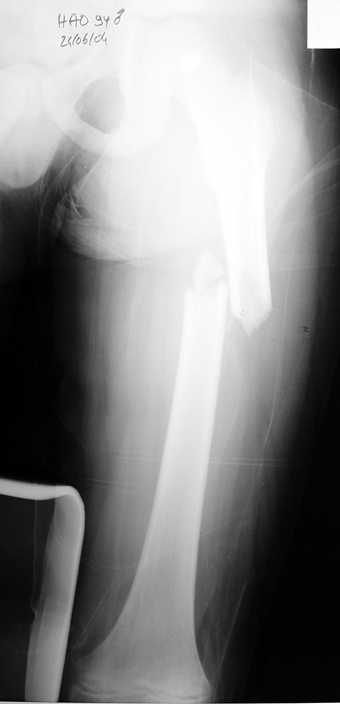

Chronic osteomyelitis leads to necrosis of bone and soft tissues. Dead bone is a nidus which hosts pathogenous microorganisms. Defence mechanisms of the host is usually not in optimum condition to deal with microorganisms. Antibiotics can’t reach the infection site because blood flow is disrupted. For these reasons, dead bone has to be completely removed by radical debridement.

Appropriate radical debridement necessitates excision of all necrotic bone and soft tissues, and frequently causes instability at the involved extremity. The remaining bone and soft tissue defect has to be fixed and reconstructed. The distraction osteogenesis method of Ilizarov is used successfully for achievement of union, correction of the deformity, elimination of limb length inequality and reconstruction of segmental bone defects.

The duration of external fixation (external fixation index) depends on the amount of distraction required, and the extremity is prone to complications during this period. After the distraction phase is completed, the external fixator remains in place during the consolidation phase, which lasts twice as long as the distraction phase; but this period is hardly tolerated. If the external fixator is removed before sufficient consolidation is achieved, fractures, deformity and shortness will be the result. In our department, ‘lenghthening over nail’ method is used in order to decrease the external fixation index and increase patient comfort and activity level. In this method, the intramedullary nail is statically locked after the completion of the distraction phase, and external fixator is removed. The extremity is stabilized by the intramedullary nail during consolidation phase. In this way, complications due to long external fixation index or early removal of the external fixator are avoided.